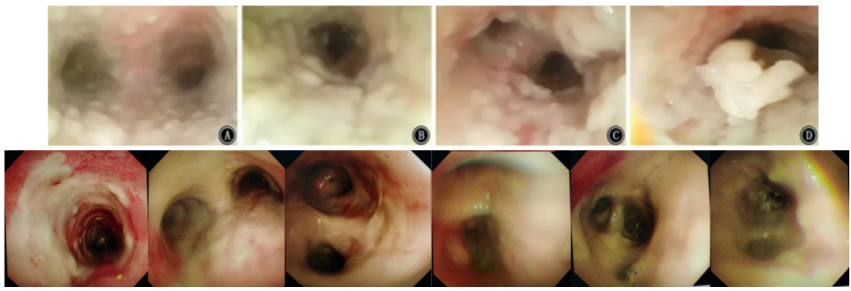

患者男性,51岁,因“咳嗽、咳痰5天,发热伴呼吸困难3天”入院。入院前曾应用静脉激素。既往有胰腺癌病史,入院后发现血糖明显升高,并确诊2型糖尿病。乙型流感病毒核酸阳性。血清GM试验阴性,BALF GM >5 S/CO,曲霉IgG阴性,BALF mNGS提示烟曲霉(序列数809975),乙型流感病毒(序列数2732),BALF培养结果为烟曲霉,对伏立康唑耐药。患者胸部CT及气管镜结果如下图所示。患者,男性,36岁,因“咳嗽、咳痰1周,呼吸困难2天”入院。入院前2天外院诊断糖尿病酮症酸中毒、乙型流感病毒性肺炎,并有使用静脉激素。入院查乙型流感病毒核酸阳性。BALF GM>5 S/CO,血清GM 4.8 S/CO,曲霉IgG阴性,BALF mNGS提示烟曲霉(序列数25173),乙型流感病毒(序列数90),气道假膜钳夹组织及BALF培养烟曲霉。患者胸部CT及气管镜结果如下图所示。IAPA的发病率较高,且在不同的流感亚型中无显著差异。而且IAPA的病死率高,但早期临床表现缺乏特异性,诊断存在一定困难,应引起临床医师的高度关注。早期、准确地识别与诊断IAPA,及时启动抗真菌治疗是改善预后的关键。[1] Iuliano AD, Roguski KM, Chang HH, et al. Estimates of global seasonal influenza‑associated respiratory mortality: a modelling study[J]. Lancet, 2018, 391(10127):1285-1300. [2] Verweij PE, Rijnders BJA, Brüggemann RJM, et al. Review of influenza‑associated pulmonary aspergillosis in ICU patients and proposal for a case definition: an expert opinion[J]. Intensive Care Med, 2020, 46(8): 1524-1535.[3] Martin-Loeches I, J Schultz M, Vincent JL, et al. Increased incidence of co-infection in critically ill patients with influenza[J]. Intensive Care Med, 2017, 43(1):48-58.[4] ABBOTT JD, FERNANDO HV, GURLING K, et al. Pulmonary aspergillosis following post‑influenzal bronchopneumonia treated with antibiotics[J]. Br Med J, 1952, 1(4757):523-525. [5] Martin-Loeches I, J Schultz M, Vincent JL, et al. Increased incidence of coinfection in critically ill patients with influenza[J]. Intensive Care Med, 2017, 43:48-58.[6] Schauwvlieghe AFAD, Rijnders BJA, Philips N, et al. Invasive aspergillosis in patients admitted to the intensive care unit with severe influenza: a retrospective cohort study[J]. Lancet Respir Med, 2018, 6(10): 782-792.[7] Beumer MC, Koch RM, van Beuningen D, et al. Influenza virus and factors that are associated with ICU admission, pulmonary co-infections and ICU mortality[J]. J Crit Care, 2019, 50:59-65. [8] Huang L, Zhang N, Huang X, et al. Invasive pulmonary aspergillosis in patients with influenza infection: a retrospective study and review of the literature[J]. Clin Respir J, 2019, 13(4):202-211. [9] Krifors A, Blennow O, Påhlman LI, et al. Influenza-associated invasive aspergillosis in patients admitted to the intensive care unit in Sweden: a prospective multicentre cohort study[J]. Infect Dis (Lond), 2024, 56(2):110-115.[10] Lu LY, Lee HM, Burke A, et al. Prevalence, Risk Factors, Clinical Features, and Outcome of Influenza-Associated Pulmonary Aspergillosis in Critically Ill Patients: A Systematic Review and Meta-Analysis[J]. Chest, 2024, 165(3):540-558. [11] Delaney JW, Pinto R, Long J, Lamontagne F, et al. The influence of corticosteroid treatment on the outcome of influenza A (H1N1pdm09)‑related critical illness[J]. Crit Care, 2016, 20:75.[12] [Nedel WL, Nora DG, Salluh JI, et al. Corticosteroids for severe influenza pneumonia: A critical appraisal[J]. World J Crit Care Med, 2016, 5(1):89-95.[13] Wauters J, Baar I, Meersseman P, et al. Invasivepulmonary aspergillosis is a frequent complication of critically ill H1N1 patients: a retrospective study[J]. Intensive Care Med, 2012, 38(11):1761-1768.[14] Rodriguez-Goncer I, Thomas S, Foden P, et al. Invasive pulmonary aspergillosis is associated with adverse clinical outcomes in critically ill patients receiving veno‑venous extracorporeal membrane oxygenation[J]. Eur J Clin Microbiol Infect Dis, 2018, 37(7):1251-1257. [15] Cavayas YA, Yusuff H, Porter R. Fungal infections in adult patients on extracorporeal life support[J]. Crit Care, 2018, 22(1):98. [16] Clancy CJ, Nguyen MH. Acute community-acquired pneumonia due to Aspergillus in presumably immunocompetent hosts: clues for recognition of a rare but fatal disease[J]. Chest, 1998, 114:629-634.[17] Hasejima N, Yamato K, Takezawa S, et al. Invasive pulmonary aspergillosis associated with influenza B[J]. Respirology, 2005;10:116-119.[18] van de Sandt CE, Bodewes R, Rimmelzwaan GF, et al, Rimmelzwaan GF, de Vries RD. Influenza B viruses: not to be discounted[J]. Future Microbiol, 2015, 10(9):1447-1465. [19] Matias G, Taylor R, Haguinet F, et al. Estimates of mortality attributable to influenza and RSV in the United States during 1997-2009 by influenza type or subtype, age, cause of death, and risk status[J]. Influenza Other Respir Viruses, 2014, 8(5):507-515.[20] Kuek LE, Lee RJ. First contact: the role of respiratory cilia in host-pathogen interactions in the airways[J]. Am J Physiol Lung Cell Mol Physiol, 2020, 319(4):L603-L619.[21] Ghoneim HE, Thomas PG, McCullers JA. Depletion of alveolar macrophages during influenza infection facilitates bacterial superinfections[J]. J Immunol, 2013, 191(3):1250-1259.[22] Fox A, Le NM, Horby P, et al. Severe pandemic H1N1 2009 infection is associated with transient NK and T deficiency and aberrant CD8 responses[J]. PLoS One, 2012, 7(2):e31535.[23] Short KR, et al. Pathogenesis of influenza induced acute respiratory distress syndrome. Lancet Infect Dis. 2014;14(1): 57-69.[24] Dewi IM, et al. Neuraminidase and SIGLEC15 modulate the host defense against pulmonary aspergillosis. Cell Rep Med. 2021;2(5): 100289.[25] Ohta H, Yamazaki S, Miura Y, et al. Invasive tracheobronchial aspergillosis progressing from bronchial to diffuse lung parenchymal lesions[J]. Respirol Case Rep, 2016, 4(1):32-34.[26] Saha BK, Chong W. A 61-Year-Old Man With Influenza Pneumonia and New Onset Hemoptysis[J]. Chest, 2021, 160(2):e181-e184.[27] 罗丹心, 谷林, 阎锡新. 体外膜肺氧合治疗重症流感相关肺曲霉病1例并文献复习[J]. 国际呼吸杂志, 2023, 43(4):448-453.[28] Park DW, Yhi JY, Koo G, et al. Fatal clinical course of probable invasive pulmonary aspergillosis with influenza B infection in an immunocompetent patient[J]. Tuberc Respir Dis (Seoul), 2014, 77(3):141-144.[29] Meersseman W, Vandecasteele SJ, Wilmer A, et al. Invasive aspergillosis in critically ill patients without malignancy[J]. Am J Respir Crit Care Med, 2004, 170(6):621-625.[30] Lahmer T, Neuenhahn M, Held J, et al. Comparison of 1,3-β-dglucan with galactomannan in serum and bronchoalveolar fluid for the detection of Aspergillus species in immunosuppressed mechanical ventilated critically ill patients[J]. J Crit Care, 2016, 36:259-264.[31] Zhu N, Zhou D, Xiong W, et al. Performance of mNGS in bronchoalveolar lavage fluid for the diagnosis of invasive pulmonary aspergillosis in non-neutropenic patients[J]. Front Cell Infect Microbiol, 2023, 13:1271853.[32] Patterson TF, Thompson GR 3rd, Denning DW, et al. Practice Guidelines for the Diagnosis and Management of Aspergillosis: 2016 Update by the Infectious Diseases Society of America[J]. Clin Infect Dis, 2016, 63(4):e1-e60. [33] Ullmann AJ, Aguado JM, Arikan-Akdagli S, et al. Diagnosis and management of Aspergillus diseases: executive summary of the 2017 ESCMID-ECMM-ERS guideline[J]. Clin Microbiol Infect, 2018, 24 Suppl 1:e1-e38. [34] Lu Y, Liu L, Li H, et al. The clinical value of Aspergillus-specific IgG antibody test in the diagnosis of nonneutropenic invasive pulmonary aspergillosis[J]. Clin Microbiol Infect, 2023, 29(6):797.e1-797.e7. [35] Donnelly JP, Chen SC, Kauffman CA, et al. Revision and Update of the Consensus Definitions of Invasive Fungal Disease From the European Organization for Research and Treatment of Cancer and the Mycoses Study Group Education and Research Consortium[J]. Clin Infect Dis, 2020, 71(6):1367-1376.[36] Springer J, White PL, Hamilton S, et al. Comparison of performance characteristics of Aspergillus PCR in testing a range of blood-based samples in accordance with international methodological recommendations[J]. J Clin Microbiol, 2016, 54(3):705-711.[37] Eigl S, Hoenigl M, Spiess B, et al. Galactomannan testing and Aspergillus PCR in same-day bronchoalveolar lavage and blood samples for diagnosis of invasive aspergillosis[J]. Med Mycol, 2017, 55(5):528-534.[38] Mengoli C, Cruciani M, Barnes RA, et al. Use of PCR for diagnosis of invasive aspergillosis: systematic review and meta-analysis[J]. Lancet Infect Dis, 2009, 9(2):89-96.[39] Springer J, Lackner M, Nachbaur D, et al. Prospective multicentre PCR-based Aspergillus DNA screening in high-risk patients with and without primary antifungal mould prophylaxis[J]. Clin Microbiol Infect, 2016, 22(1):80-86.[40] 施毅, 赵江南. 侵袭性真菌病病原学非培养实验室诊断方法[J]. 中华结核和呼吸杂志, 2019, 42(7):500-505[41] Eigl S, Prattes J, Lackner M, et al. Multicenter evaluation of a lateral-flow device test for diagnosing invasive pulmonary aspergillosis in ICU patients[J]. Crit Care, 2015, 19(1):178.[42] Jenks JD, Mehta SR, Taplitz R, et al. Point-of-care diagnosis of invasive aspergillosis in non-neutropenic patients: aspergillus galactomannan lateral flow assay versus aspergillus-specific lateral flow device test in bronchoalveolar lavage[J]. Mycoses, 2019, 62(3):230-236.[43] Maertens JA, Raad II, Marr KA, et al. Isavuconazole versus voriconazole for primary treatment of invasive mould disease caused by Aspergillus and other filamentous fungi (SECURE): a phase 3, randomised-controlled, non-inferiority trial[J]. Lancet, 2016, 387(10020):760-769.[44] Maertens JA, Rahav G, Lee DG, et al. Posaconazole versus voriconazole for primary treatment of invasive aspergillosis: a phase 3, randomised, controlled, non-inferiority trial[J]. The Lancet, 2021, 397(10273):499-509.[45] Thompson 3rd GR, Soriano A, Cornely OA, et al. Rezafungin versus caspofungin for treatment of candidaemia and invasive candidiasis (ReSTORE): a multicentre, double-blind, double-dummy, randomised phase 3 trial[J]. Lancet, 2023, 401(10370):49-59.[46] Shaw KJ, Ibrahim AS. Fosmanogepix: A Review of the First-in-Class Broad Spectrum Agent for the Treatment of Invasive Fungal Infections[j]. J Fungi (Basel), 2020, 6(4):239. [47] Petraitis V, Petraitiene R, Katragkou A, et al. Combination Therapy with Ibrexafungerp (Formerly SCY-078), a First-in-Class Triterpenoid Inhibitor of (1→3)-β-d-Glucan Synthesis, and Isavuconazole for Treatment of Experimental Invasive Pulmonary Aspergillosis[J]. Antimicrob Agents Chemother, 2020, 64(6):e02429-19.[48] Wiederhold NP. Review of the Novel Investigational Antifungal Olorofim[J]. J Fungi (Basel), 2020, 6(3):122. [49] Zhou M, Liu L, Cong Z, et al. A dual-targeting antifungal is effective against multidrug-resistant human fungal pathogens[J]. Nat Microbiol, 2024, 9(5):1325-1339.